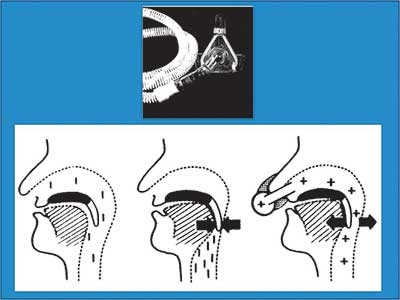

Η θεραπεία του ΣΑΑΥ πρωταρχικώς είναι συντηρητική. Στα µέτρα που βοηθούν στη βελτίωση της κλινικής εικόνας, συγκαταλέγονται η απώλεια βάρους, η διακοπή αλκοόλ, η αποφυγή κατασταλτικών φαρµάκων και η αποφυγή ύπνου σε ύπτια θέση. Η αποτελεσµατικότερη συντηρητική θεραπεία είναι ο µη επεµβατικός µηχανικός αερισµός µε θετική πίεση (Continuous Positive Airway Pressure – CPAP) κατά τη διάρκεια του ύπνου. Η θετική πίεση (5 µε 15 cmH2O) εφαρµόζεται στον αεραγωγό µέσω ρινικής µάσκας. Ο κύριος µηχανισµός δράσης του CPAP συνίσταται

Εικόνα 2

στην παρεµπόδιση της σύµπτωσης (collapse) των ανώτερων αεραγωγών µε διατήρηση της ενδοαυλικής πίεσης πάνω από την κρίσιµη πίεση σύγκλεισης του φάρυγγα – υποφάρυγγα (critical closing airway pressure). Η εφαρµογή της πίεσης µέσω της ρινικής οδού προκαλεί την επαφή της µαλακής υπερώας µε τη βάση της γλώσσας, µε αποτέλεσµα να ελαχιστοποιείται η διαφυγή αέρα από το στόµα (Εικόνα 2).